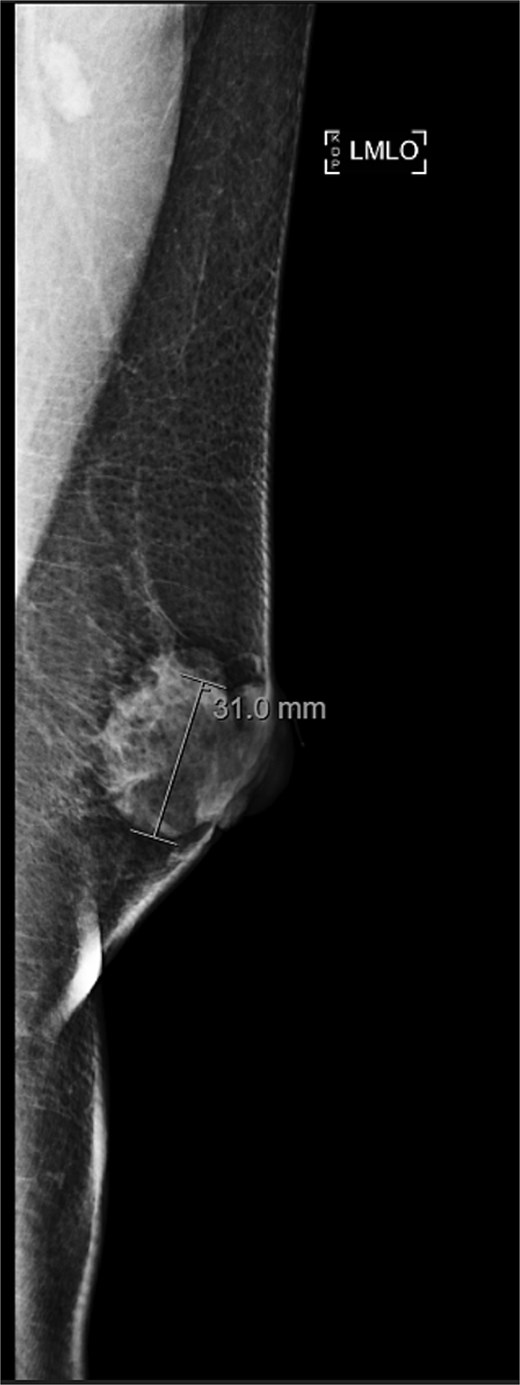

A 63-year-old male with a past medical history of heavy daily tobacco use, COPD, and a left breast leiomyoma diagnosed in 2018 presented to a general surgeon with a nonhealing left breast abscess. The patient had a persistent 3 cm retroareolar mass despite multiple incision and drainage procedures. On exam, the left axillary lymph nodes were unremarkable and the nipple, while not inverted, was chronically distorted, indurated, and inflamed. The persisting mass and inflammation were initially concerning for inflammatory breast cancer. Superficial biopsy by both a dermatologist and general surgeon were equivocal. Diagnostic mammogram and targeted left breast ultrasound revealed a retroareolar 3.3 × 3.6 × 2.7 cm heterogenous mass, corresponding to the area of palpable concern (Figs 1 and 2).

Diagnostic mammogram of left breast showing heterogenous retroareolar mass – second view.